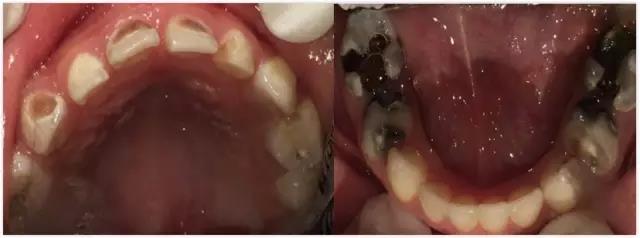

先来说说蛀牙是什么?北京儿童医院口腔科副主任医师高艳霞介绍,从时间角度讲,蛀牙是一个慢性病。蛀牙是指牙齿从浅到深一系列的改变,从最开始的白垩色,通俗的说就是发现孩子的牙齿不那么透亮,到雾状变化,再到开始变软,有黑色、褐色的变化,出现掉渣的情况,直到发展成明显的蛀牙。

图/北京儿童医院口腔科